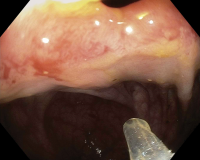

Close endoscopic view of tissue with a medical instrument entering.

Close endoscopic view inside a hollow organ.

Endoscopic therapy for stricture after